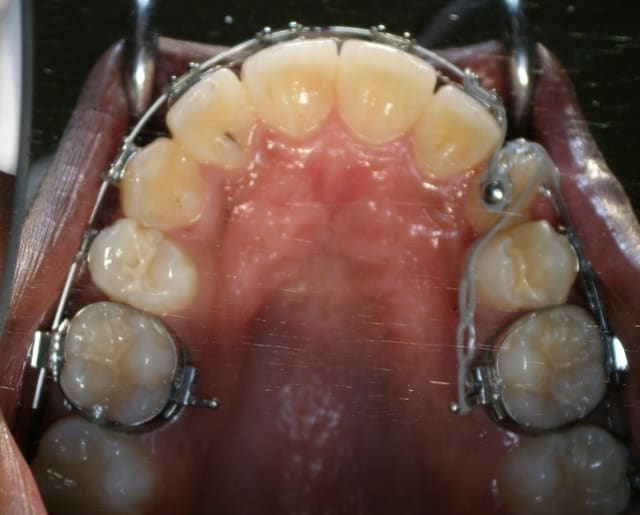

Pour ce cas collage de l'arcade 15 jours avant

sur la photo 2 on distingue les 2 germes l'un au dessus de l'autre (eh non pxav je n'y arrive tjrs pas pour les photos)

trajet , "excision" sinon cela saigne un peu trop, dégagement de la couronne a minima,collage pose de la chainette en traction, régularisation des cretes, sutures

Pour info, il est préférable :

1. de faire le collage avec un anneau ou bouton à bords mousses, afin de limiter le traumatisme de la gencive. Le bracket sera positionné en supra-gingival. Il est de toute façon quasiment impossible de le placer correctement en première intention.

2. d'utiliser un auxiliaire métallique ( ligature avec toron, chainette or...) dans la partie sous muqueuse et de réserver la chainette ou fil élastomérique à la zone supra-gingivale.